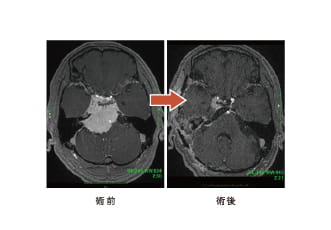

髄膜腫(特に頭蓋底部)

65歳男性、頭蓋底部巨大髄膜腫、外科手術のみ